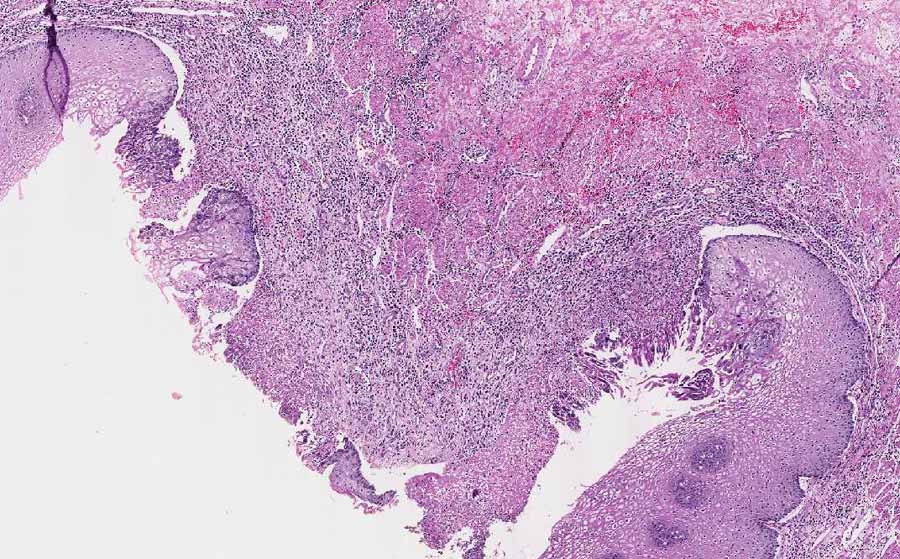

• This is a resection specimen which shows several characteristic features of esophagitis caused by herpes simplex virus (herpes eesophagitis). First there are multiple ulcers (Area 1 and 2) with intervening intact mucosa (arrow). The ulcer is covered by a thin layer of fibrinous exudate with inflammatory cells. Underlying this fibrinous exudate are granulation tissue with acute and chronic inflammatory cells.

• At the edge of both ulcers, there are multinucleated cells. These nuclei are the so called 3M nuclei which stands for molding of nuclei, margination of chromatin, and multinucleated. It is important to note that these nuclei are typically found at the edge of the biopsy specimen. If the endoscopist has biopsied only the center of the ulcer, it may be difficult to establish the diagnosis based on histopathology alone.